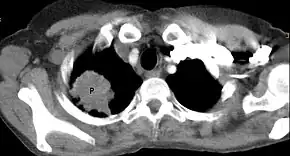

![]() | |

| Chest radiograph showing a Pancoast tumor (labeled as P, non-small cell lung carcinoma, right lung), from a 47-year-old female smoker. | |